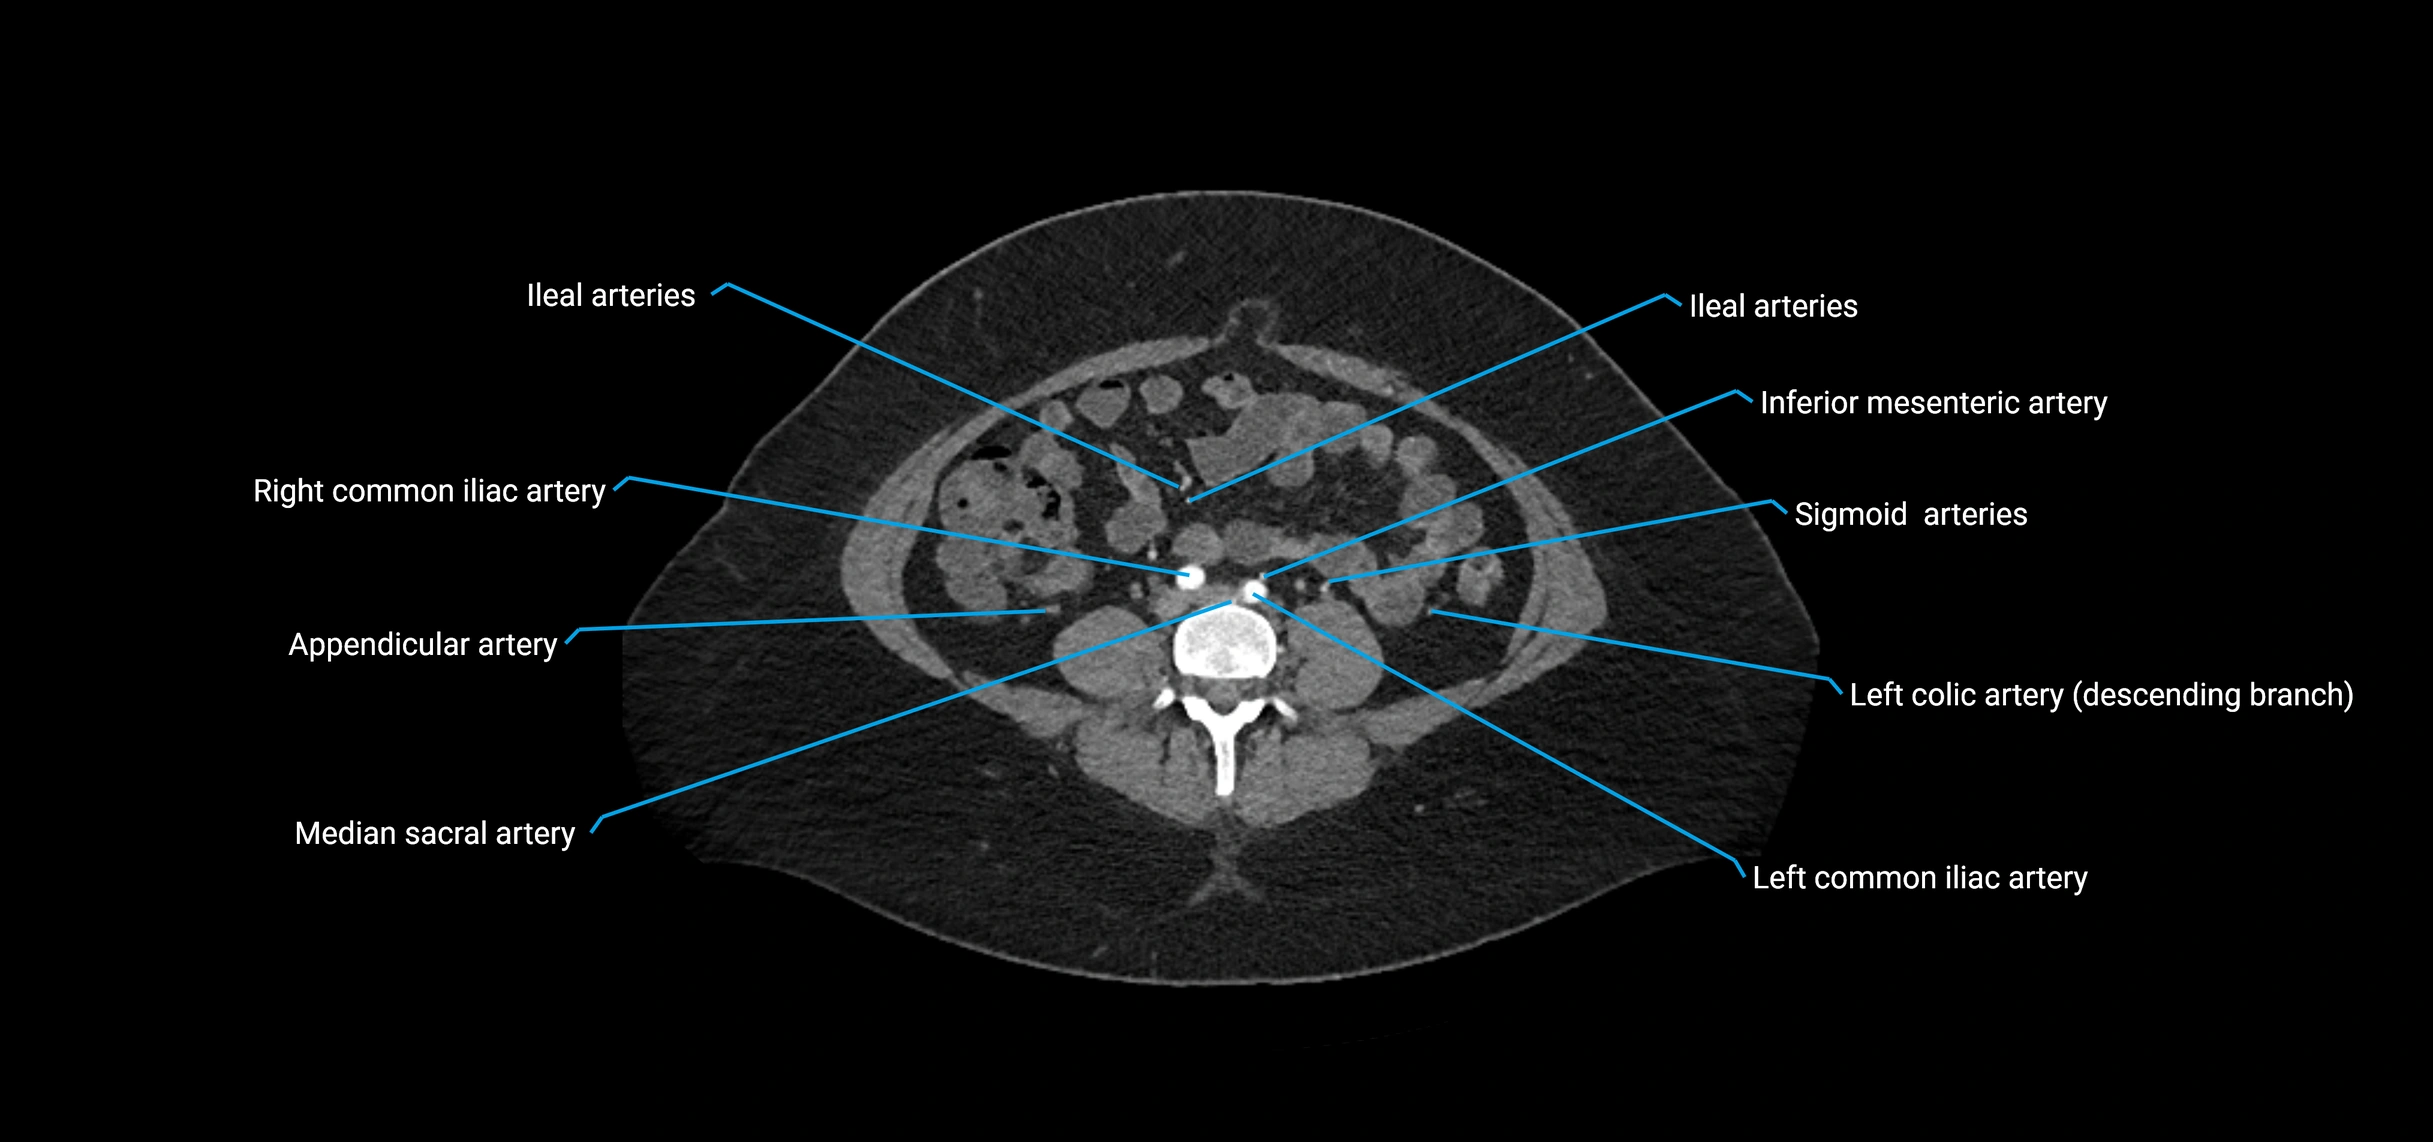

Contrast-enhanced CT (CTA):

• Gold standard for abdominal aortic imaging

• Provides excellent detail of lumen, wall, aneurysm, thrombus, and branch vessels

• Multiplanar and 3D reconstructions help in aneurysm measurement, stent graft planning, and dissection evaluation

• Detects acute rupture, traumatic injury, or occlusion with high sensitivity